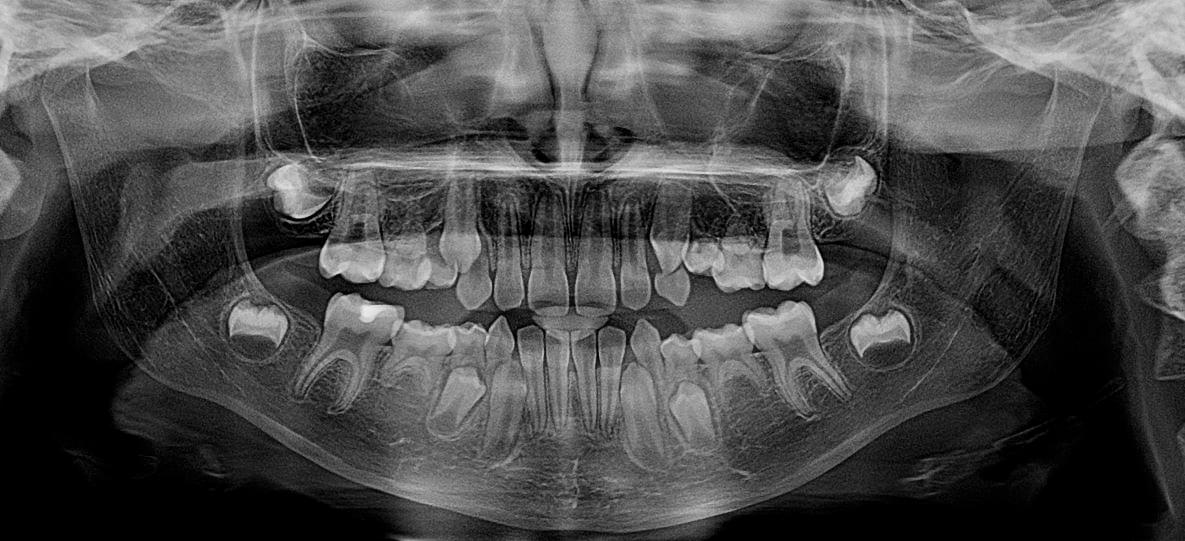

Ортопантомограма (ОПТГ) — це як загальна "фотографія" всіх ваших зубів та щелеп на одному знімку. Це швидке і безпечне 2D-сканування, під час якого апарат робить круговий рух навколо вашої голови, щоб отримати повне зображення.

● Стоматолог бачить стан усіх зубів, одночасно на одному фото.

● Для ортодонтів (вирівнювання зубів) та перед видаленням зубів

мудрості.

● Дозволяє оцінити розвиток зубів у дітей.